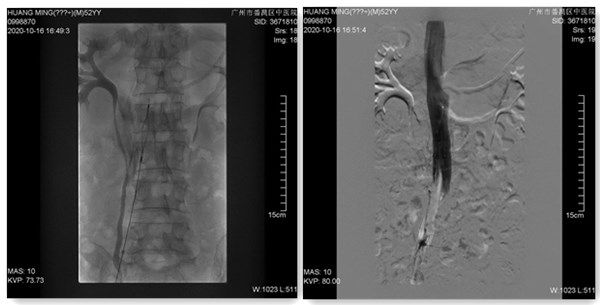

图1:腔静脉滤器经引导导管释放图 2:腔静脉滤器已置入下腔静脉,并行下腔静脉造影

心血管内科祁家祥主任与陈钜深医师为患者实施了下腔静脉滤器置入术,并为患者成功置入可回收腔静脉滤器。手术顺利结束,术后患者无不适反应,安返病房。